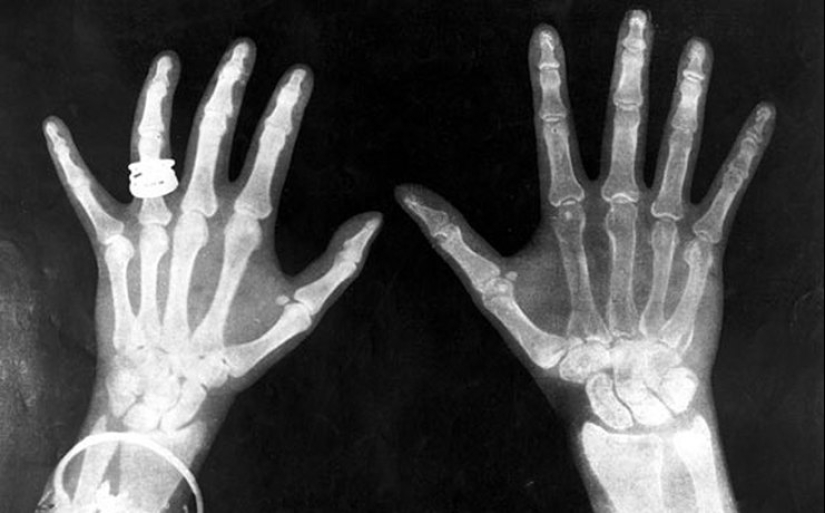

X-rays

Everyone at least once in life got to the diagnosis through x-ray machine. The discovery of x-rays was a breakthrough in medicine and other fields. Cosmetology also tried to use the invention. X-ray was considered a reliable means of hair removal. After a few sessions the unwanted hair fall out. At the same time, grew old, grew thin skin. The most terrible consequences took place in a few years. Waxing with the help of x-ray machine led to an increase in the incidence of skin cancer.